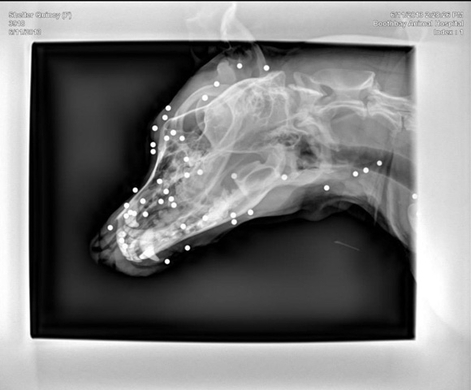

高齢の小型犬は要注意 咳を起こす心不全と肺水腫 アイビーペットクリニック